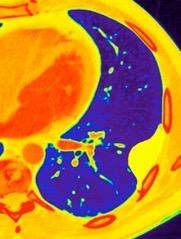

En el hemotórax, los elementos formes de la sangre tienden a depositarse en la parte más declive

Polireddy K et al. Blunt thoracic trauma: role of chest radiography and comparison with CT findings and literature review . Emerg Radiol 2022.

Neumo-Hemotórax

Sin fracturas: 6,7%

1-2 fracturas: 24,9% + de 3 fracturas:81,4%

Colección pleural

Hemorrágica.30-70 UH

Extravasación iv con sangrado activo.>90 UH “Simpático”..<15 UH